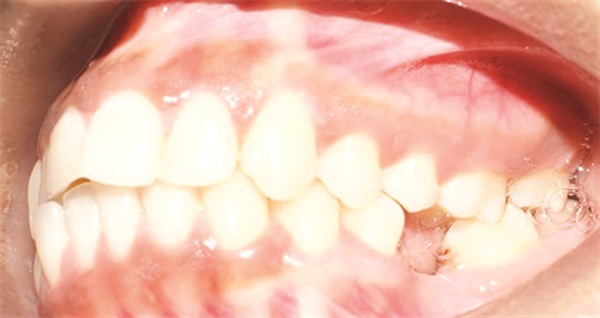

The diagnostic findings told a more complicated story. The patient presented with a skeletal Class II relationship, bilateral Class I molar and canine relationships, collapsed arches, and proclined incisors in both arches. Both midlines were shifted to the right. She also exhibited crossbite of the upper right first molar and upper right lateral incisor, a discrepancy between centric relation and centric occlusion, and a noticeable cant in the lower anterior segment. Her dental history included previous extractions of the upper right third molar and upper left second molar (Figs. 1–12).

Fig. 3